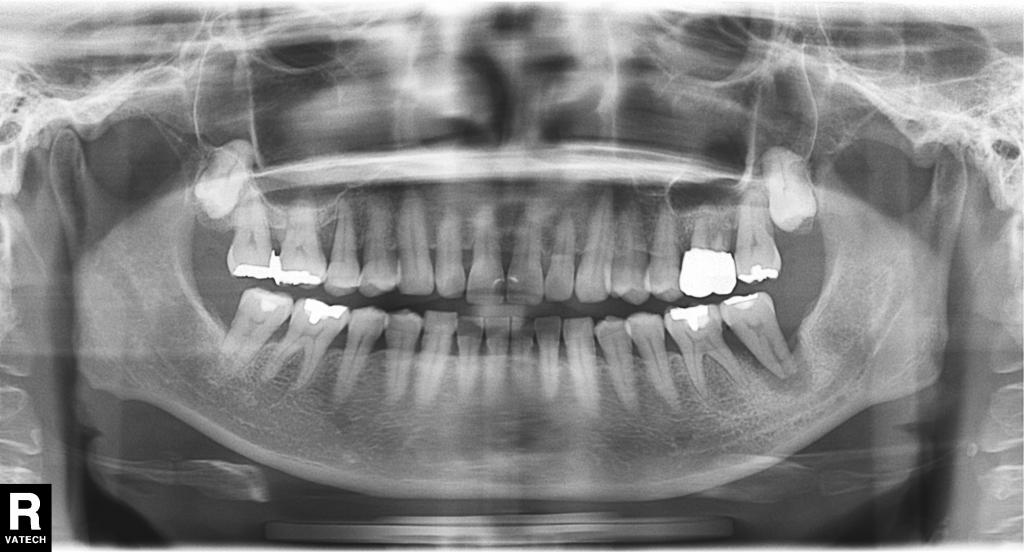

- 全体のレントゲン写真です。

左下奥歯の周りの骨は大きく吸収し、「浮いている様な状態」でした。